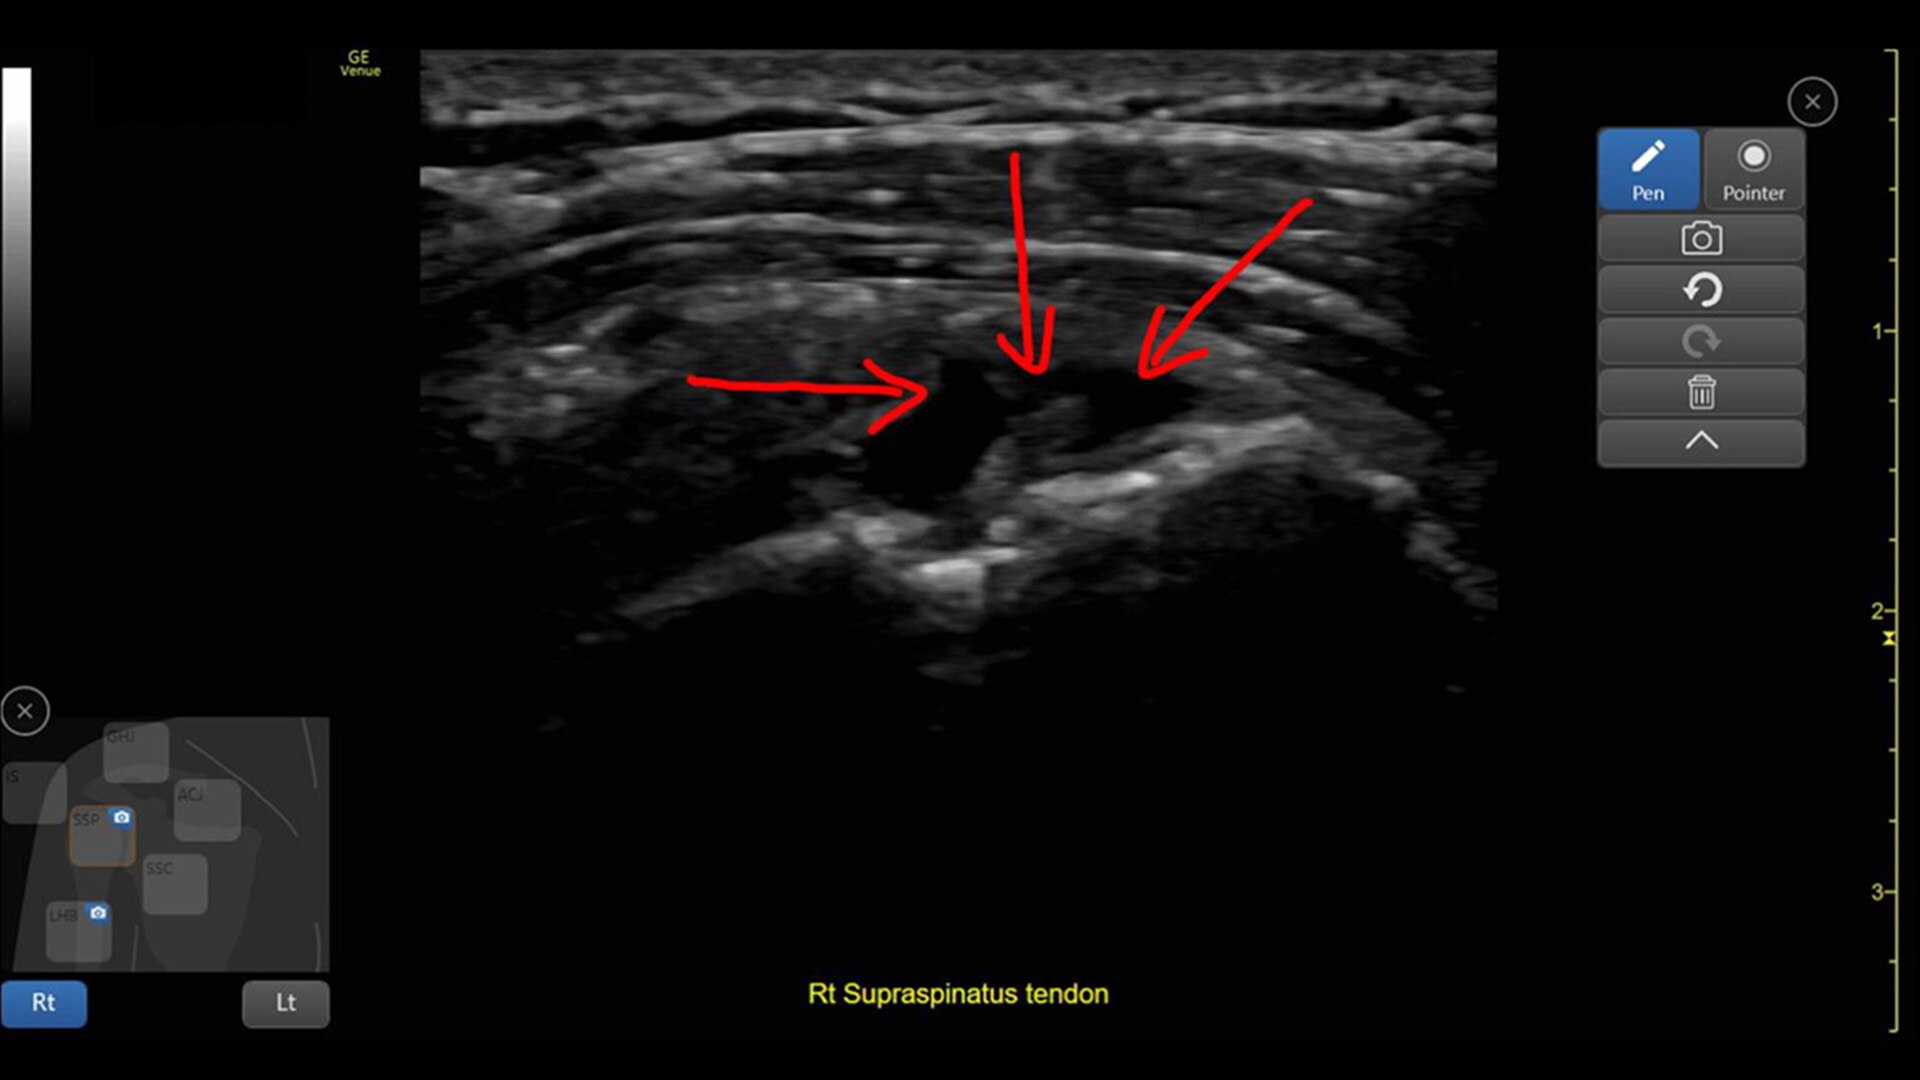

CATHETER TO VESSEL RATIO

Accurate catheter selection tool

Selecting the wrong sized catheter can lead to catheter related thrombosis.1 Catheter to Vessel Ratio is a measurement tool that supports clinicians in selecting the appropriate sized catheter based on vessel diameter.